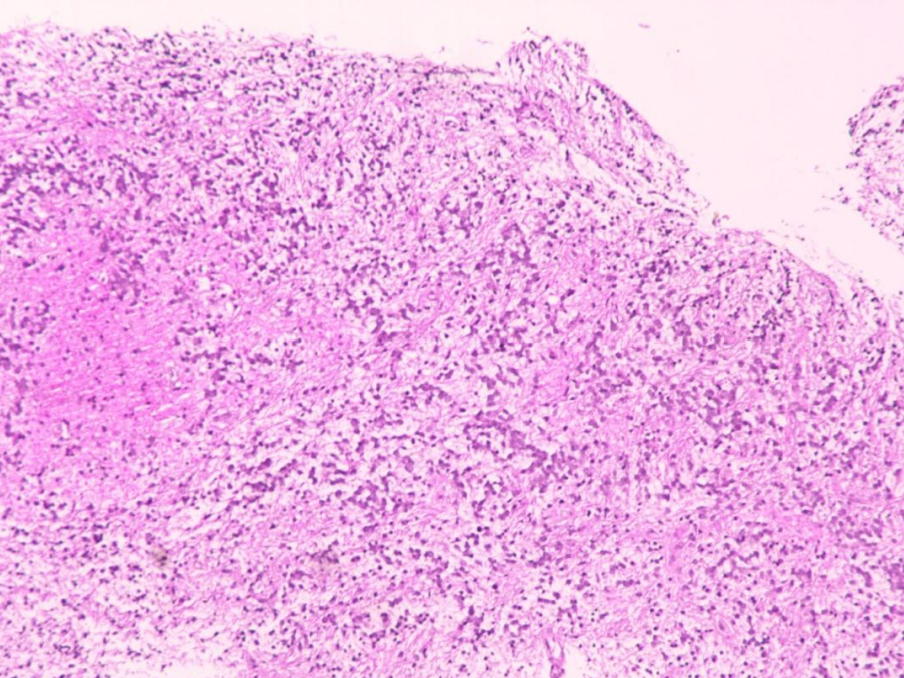

整合诊断:弥漫中线胶质瘤, H3K27变异型(H3K27M突变)

组织病理学类型:胶质母细胞瘤

CNS WHO 级别:4级

分子检测:未做

组织学特征:肿瘤弥漫性生长、细胞密度高、间质富于粘液、细胞呈缎带样排列、部分胞浆空 亮、核分裂1个/10HPF、未见栅栏样坏死及血管内皮增生。

免疫组化:B1-01(2、(左脑室后角肿瘤)):GFAP(+), Olig2(+), Vimentin(部分+), Nestin(+), Synaptophysin(-), NFP(+), INI1/SMARCB1(存在), NeuN(-), Chromogranin A(-), IDH1(R132H)(-), ATRX(存在), p53(+), H3 K27M(+), H3 K27me3(缺失), H3.3 G34R(-), CD34(脉管+), BRAF V600E(-), Ki-67(20%+), MLH1(存在), MSH2(存在), MSH6(存在), PMS2(存在), MAP-2a.b.c(+)。